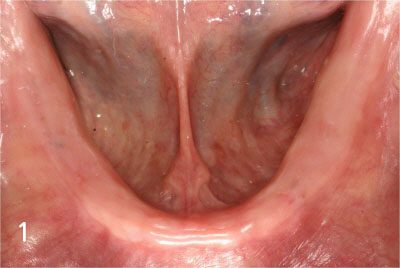

Gum bone is depressed after extraction